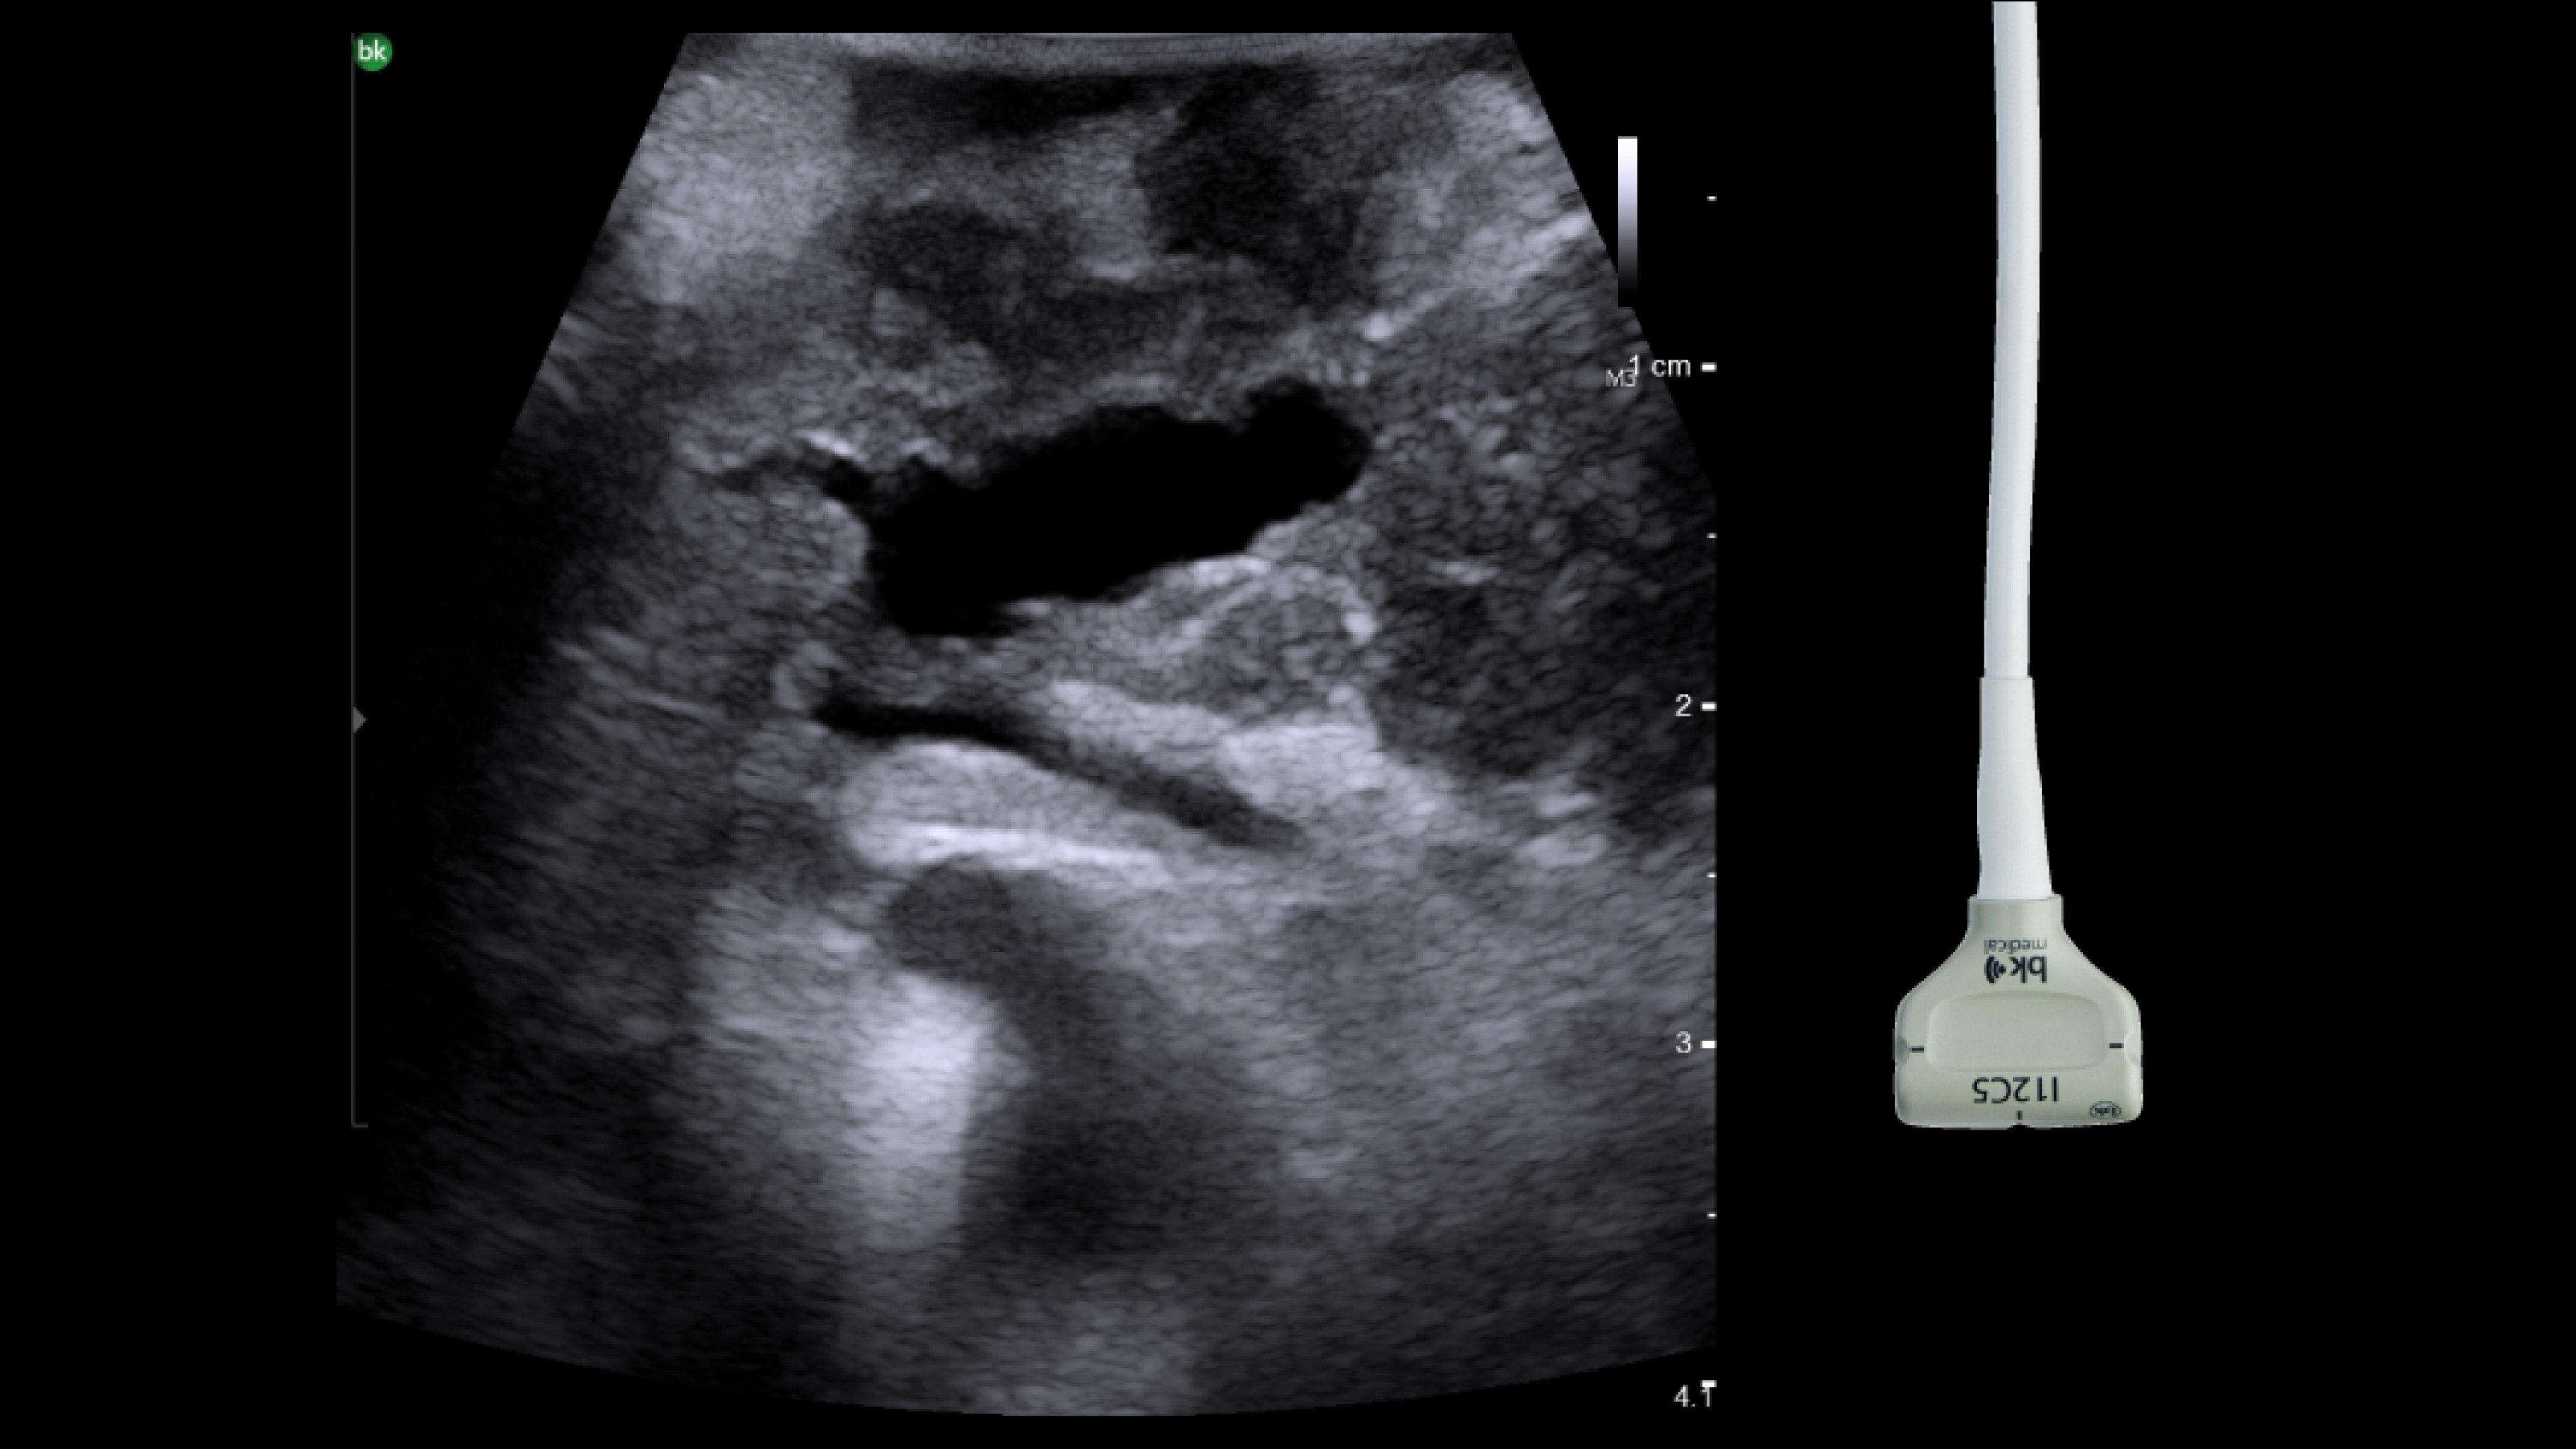

Resection ultrasound

Active imaging supports liver and pancreas tumor resection procedures by helping you visualize complex anatomical variations and relationships to vascular structures, identify tumor location, define adequate margins of resection, and assess surgical planning.

Active imaging with intraoperative ultrasound supports critical decision-making in open or minimally invasive tumor resections.

• Visualize complex anatomical variations.

• Identify tumor location, proximity, and invasion of vasculature.

• Define adequate margins of resection.

• Understand relationship to vascular structures.

• Assess surgical planning and check for vessel patency at the end of the procedure.